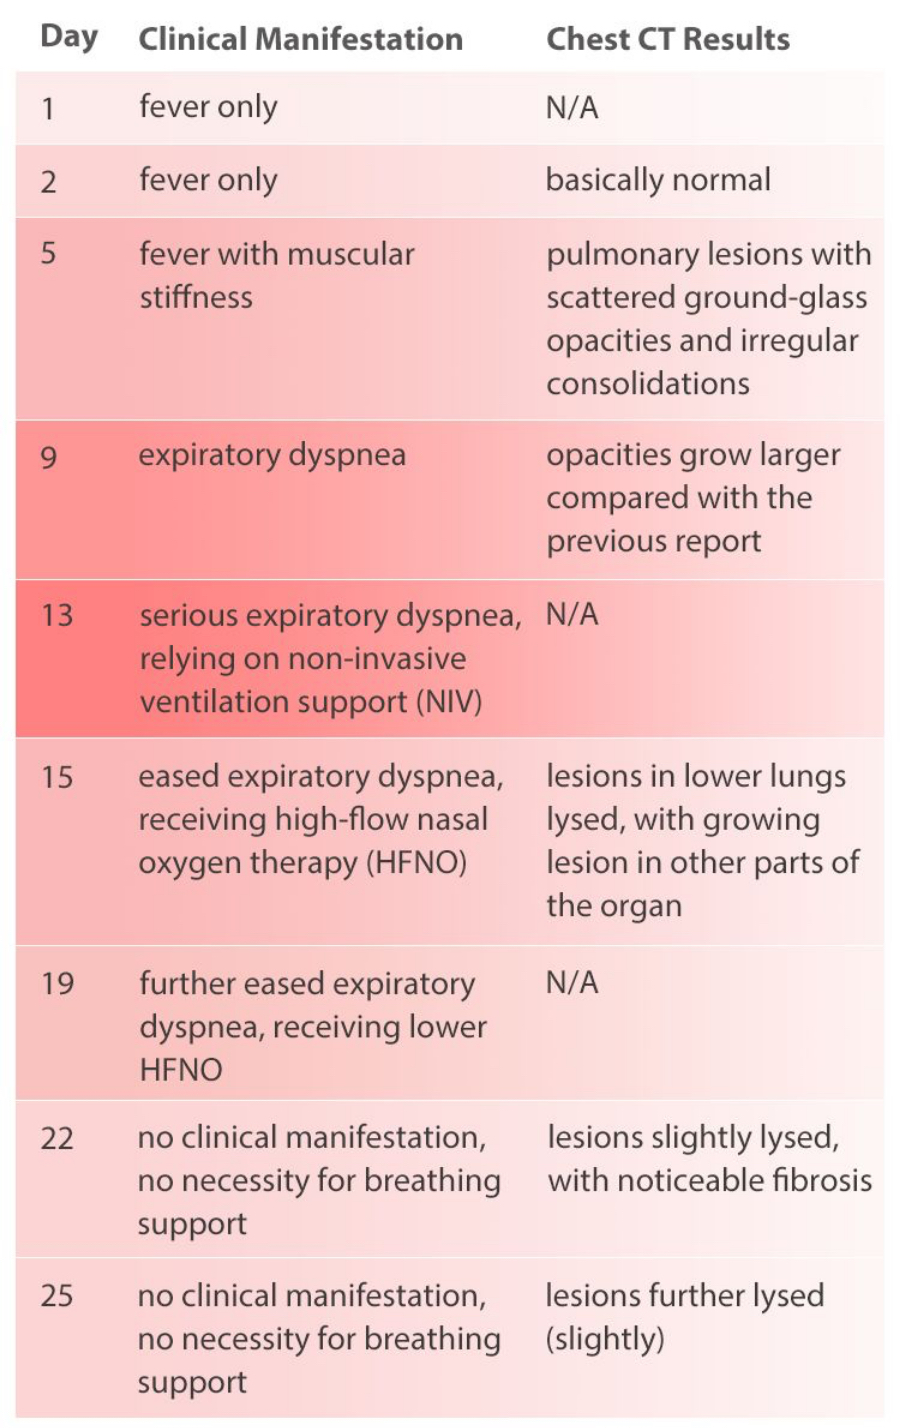

The patient being monitored in the study had a history of close contact with individuals from Wuhan. The patient registered low fever 5 days before admission with no other symptoms, and the CBC and CRP results were normal. Re-examination on the day after showed a slight decrease of WBC and a slight increase of CRP value. Levofloxacin tablets were taken orally following doctor's instruction for anti-infective treatment. On the day of admission, the patient had a high fever (maximum 39Ōäā). Chest CT scan showed pulmonary lesions with scattered ground-glass opacities and irregular consolidations. The patient was given a presumptive diagnosis as a suspected case of COVID-19.

During the whole process of diagnosis and treatment, the patientŌĆÖs clinical manifestations and chest CT scan results have been recorded (see Table 1), and so are CBC and CRP results (see Figure 1).

The patient in this case got fever as the first symptom, with a clear epidemiological history (close contact with another person returning from Wuhan). Chest CT scan before admission suggested that this was probably a viral pneumonia patient who was later confirmed as a COVID-19 patient after nucleic acid test. After admission, the patient's breathing gradually worsened to respiratory failure. After mechanical ventilation and other treatments related, the clinical symptoms basically disappeared with improved imaging results. The patient was discharged after two negative results of nucleic acid test.

The patient had a low fever at the time of the initial examination, but the WBC count and lymphocyte count were normal, suggesting that the patient was in the early stage of COVID-19 at that time.

As the patientŌĆÖs health deteriorated, the white blood cell count (WBC#) and neutrophil count (Neu#) increased sharply after a slight decline, while the lymphocyte count (Lym#) continued to decline. The Neutrophil-to-Lymphocyte Ratio (NLR) rose rapidly while the CRP value goes up. At the most critical moment (the 13th day after the onset of symptoms), WBC#, Neu#, NLR and CRP reached their peaks respectively, with Lym# at the lowest point.

After proper medical treatment and caring, the patient gradually recovered, with rapid decline of WBC#, Neu#, NLR and CRP. In contrast, Lym# gradually increased. On the 25th day, WBC#, Neu#, NLR, Lym# and CRP all returned to normal range. Although CT scan showed that the lesions in lungs hadnŌĆÖt completely disappeared yet, the patient was already able to move without oxygen therapy. Most importantly, the nucleic acid test result turned negative.

An NLR greater than 3.13 can be used as an independent predictor for the exacerbation of patients with COVID-19. The finding of this case is consistent with that in the study published by Ditan Hospital. The patientŌĆÖs NLR was higher than 3.13 from the 9th day to the 22nd day, and the NLR drops below 3.13 on the 25th day. In this case, PCT was monitored on Day 5, 13, and 22, all of which were lower than 0.5 ng/mL, indicating that no serious bacterial infection occurred.